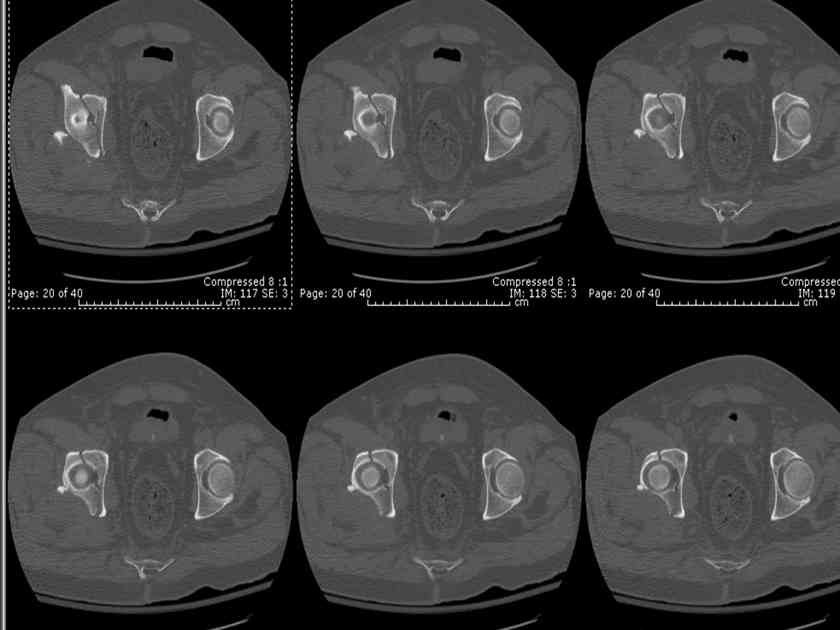

You can adjust the quadrilateral surface contact point as needed to get the fracture to reduce...we plan this based on the fracture orientation on the preop CT scan images...the clamp should be balanced to avoid over compressing one portion and distracting the other limb. Go back to and you¹ll see on the injury CT where the clamp tines need to be.

Here's a pic from the foot of the bed and you can see the clamp in the wound and the knee is extended so he must've had a tight rectus. The C-arm is rolled back to an obturator oblique image to reveal the anterior column...we put a slight outlet tilt to combine the images and give a better view of the anterior column...we can see the posterior column limb reduction in the wound, we can palpate the quadrilateral surface limb, and the image demonstrates the anterior column portion...you can adjust the tilt and rotation to image tangentially to the fracture plane if you'd like. We've inserted a 2mm K wire to site the starting point and aim/orientation for the drill and screw

A CT scan will rarely lie to you...reveals your reduction and implants...we use it to assess, teach, grade, and try to get better next time.